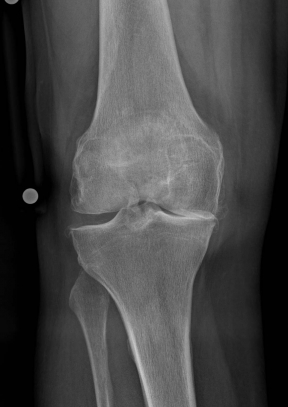

X-rays can be used to reliably diagnose the extent of joint wear. In the case of high-grade gonarthrosis, for example, the joint space and the formation of jagged edges (bone attachments, "osteophytes") as well as axial malalignment can be detected. If additional damage to the internal structures of the knee is suspected, ultrasound examination (sonography) or magnetic resonance imaging (MRI) can help clarify the situation.

Example X-ray images before and after implantation of a Persona knee prosthesis with robot.

| a) präoperative Röntgenbilder des kranken Knies in 2 Ebenen | |